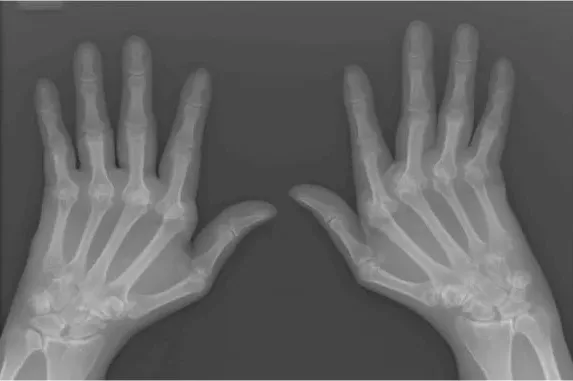

Artritis je vodeći uzrok invaliditeta i može značajno otežati svakodnevni život. Mnogi traže učinkovite metode za ublažavanje boli, no reumatolog dr. Julius Birnbaum upozorava da postoje dvije popularne, ali nepreporučene metode liječenja – opioidni lijekovi i injekcije glukozamina u zglobove.